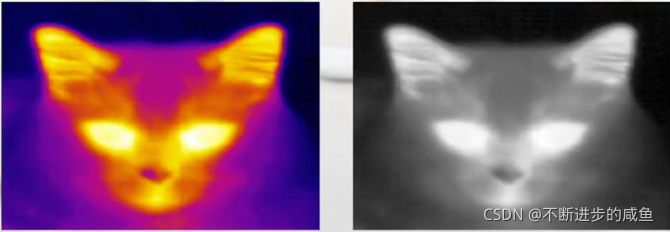

(4)伪彩图像: 红外图像更能表达自然界中温度的变化(右,猫眼睛耳朵亮),为了更能表现温度的变化,科学家们使用伪彩的方式把红外图像描述出来,更能逼真表示温度变化

(2)红外图像: 红外图像更能表达自然界中温度的变化(猫眼睛耳朵亮)